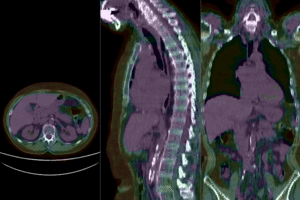

this is the baseline PET/CT exam

fixed image/target

baseline PET/CT

moving image

follow-up PET/CT